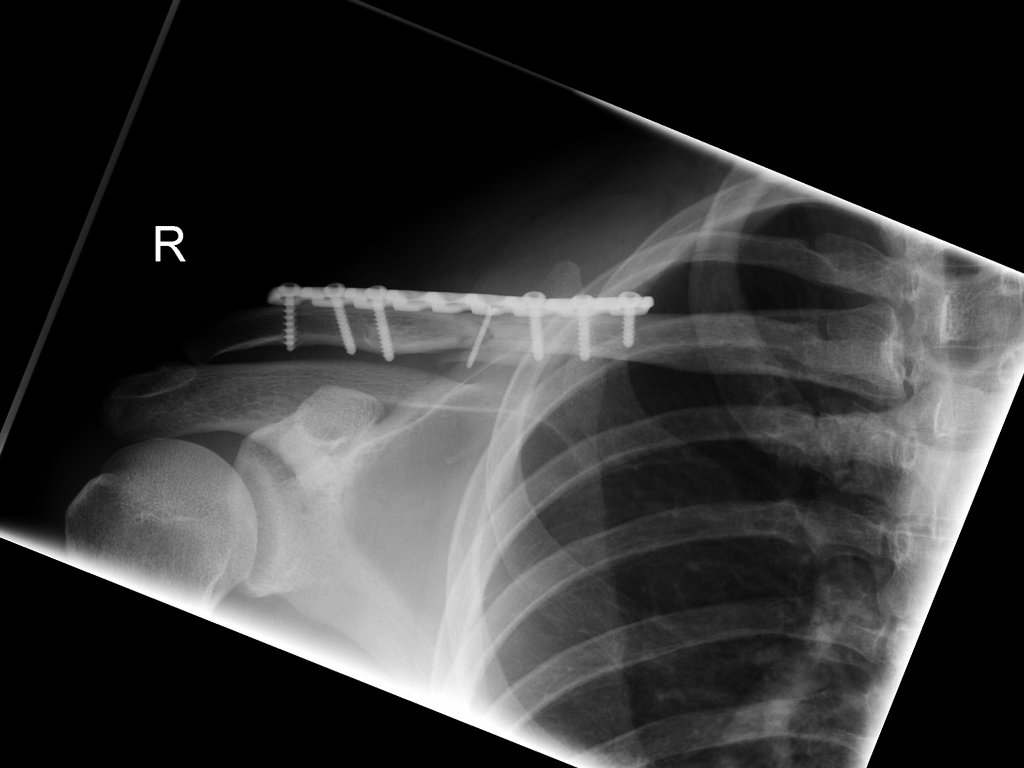

Clavicula-Fraktur (23./25. Juli/2. August 2007)